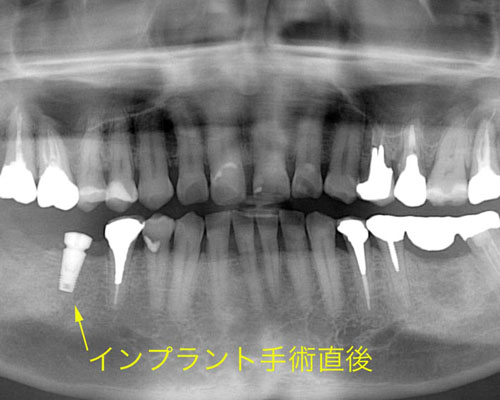

1本目のインプラント

右の一番奥は、抜いて間もなく骨が十分固まっていなかったために、インプラントを入れることができず、手前の1本だけインプラントを入れました。インプラント手術をした後は、その周囲でしばらく噛むことができません。